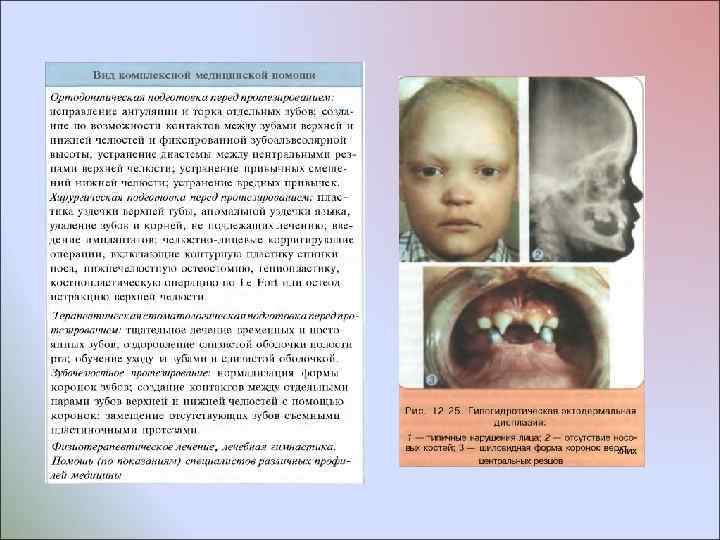

Врожденное отсутствие более 10 постоянных зубов У некоторых пациентов отмечают врожденное множественное отсутствие зубов без изменения развития других производных эктодермы У пациентов с ГЭД мало волос, они светлого цвета, брови недоразвиты, ресницы растут кустиками; кожа сухая, морщинистая, нередко пигментированная вокруг глаз и рта; ногти деформированы; зрение нарушено - пользуются очками с детства. По эстетическим отклонениям, состоянию психоневротического статуса и общим нарушениям организма пациенты этих двух групп различаются. Общим для них является лишь врожденное отсутствие зачатков более 10 постоянных зубов

Врожденное отсутствие более 10 постоянных зубов У некоторых пациентов отмечают врожденное множественное отсутствие зубов без изменения развития других производных эктодермы У пациентов с ГЭД мало волос, они светлого цвета, брови недоразвиты, ресницы растут кустиками; кожа сухая, морщинистая, нередко пигментированная вокруг глаз и рта; ногти деформированы; зрение нарушено - пользуются очками с детства. По эстетическим отклонениям, состоянию психоневротического статуса и общим нарушениям организма пациенты этих двух групп различаются. Общим для них является лишь врожденное отсутствие зачатков более 10 постоянных зубов